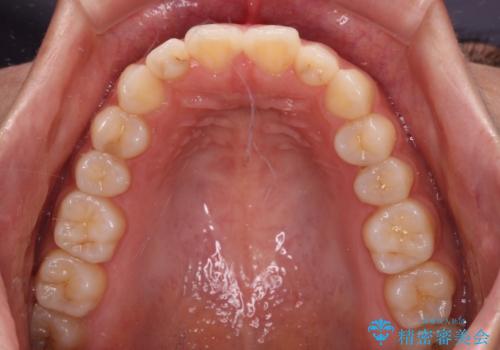

インビザラインを用いた上顎の部分矯正

- 上顎前歯の叢生を気にして来院された患者様です。

下顎前歯や上下奥歯の咬み合わせには殆ど問題がないため、上顎前歯のみを矯正する治療を提案しました。

ワイヤー装置でもインビザラインでも可能でしたが、前歯のみをきれいに排列するのであればインビザラインの方が仕上がりが良いので、インビザライン・ライトにて治療を行うこととしました。